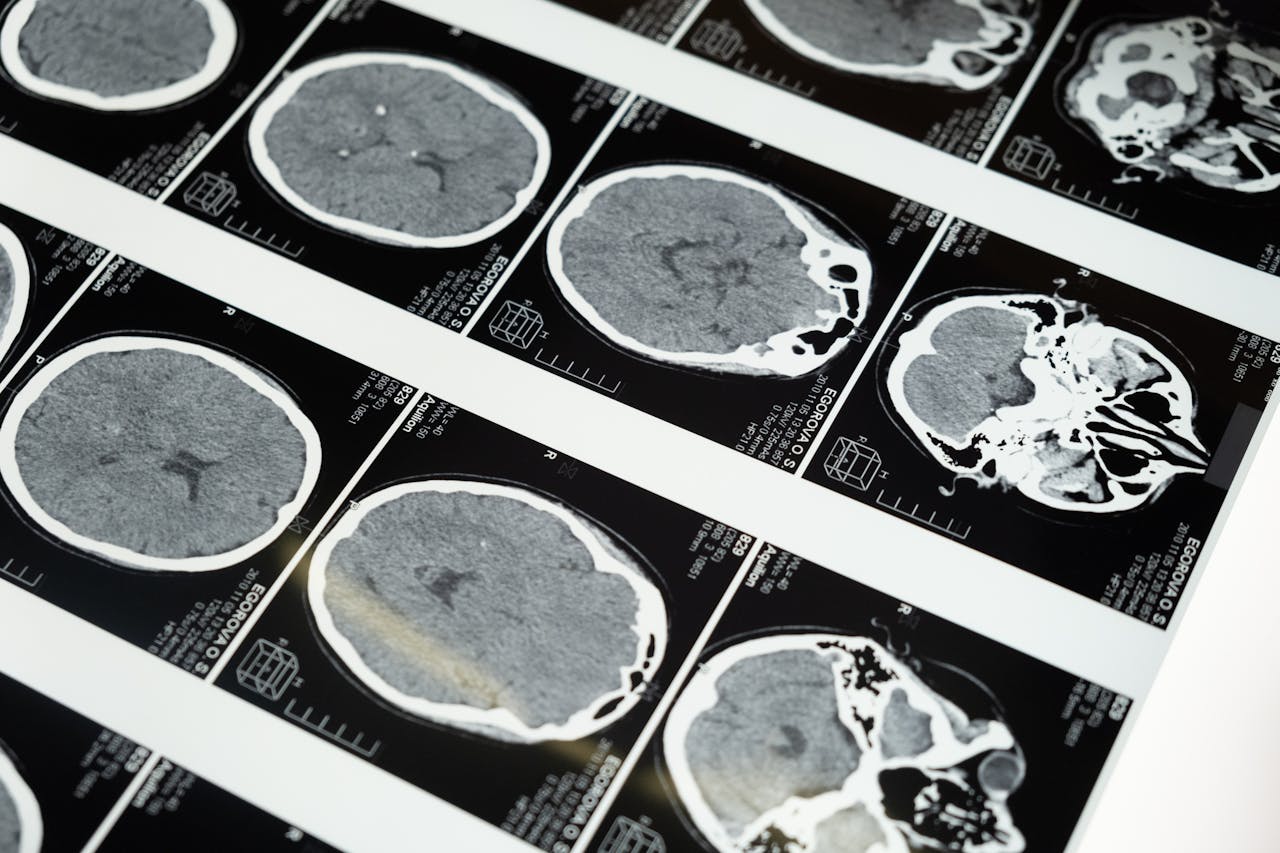

How Your Brain Rewires Itself Every Time You Learn Something New